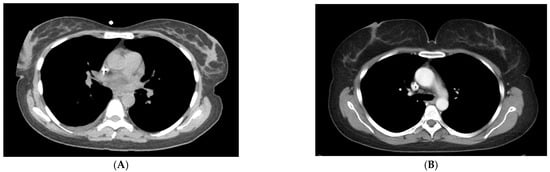

Figure 4. Right upper outer quadrant microcalcifications on craniocaudal mammography were recommended for biopsy (A). Axial chest CT performed 128 days prior to the mammogram recommended biopsy for a 20 mm right upper outer quadrant mass (B). Biopsy results at the time of mammography were ductal carcinoma in situ.

Figure 5. Craniocaudal mammographic image reveals clustered left breast microcalcifications that were recommended for biopsy (A). Contrast chest CT in axial projection on the same day reveals a 20 mm mass with an average HU of 61 (B). Biopsy results were invasive breast cancer.

3.4. Calcifications

Microcalcifications were identified on twenty mammograms, and biopsy was recommended in five (25%). In total, 2/20 (10%) patients with micro-calcifications on mammography had breast cancer. No micro-calcifications were identified on CT. In patients who had micro-calcifications on mammography, CT correctly diagnosed two true positive nodules (Figure 4 and Figure 5), one of which was ductal carcinoma in situ and the other was invasive breast cancer. The remaining eighteen patients with microcalcifications on mammography were correctly identified as normal on chest CT.

We were concerned about the inability of CT scan to recognize micro-calcifications. Twenty patients had microcalcifications on mammography, of which two were cancer. CT correctly diagnosed these two patients because a nodule was seen on CT in the area of microcalcifications. A nodule was not identified on mammography for these two patients. The findings suggest that, like MRI, CT may diagnose the most clinically relevant microcalcifications, but further investigation is needed [17].